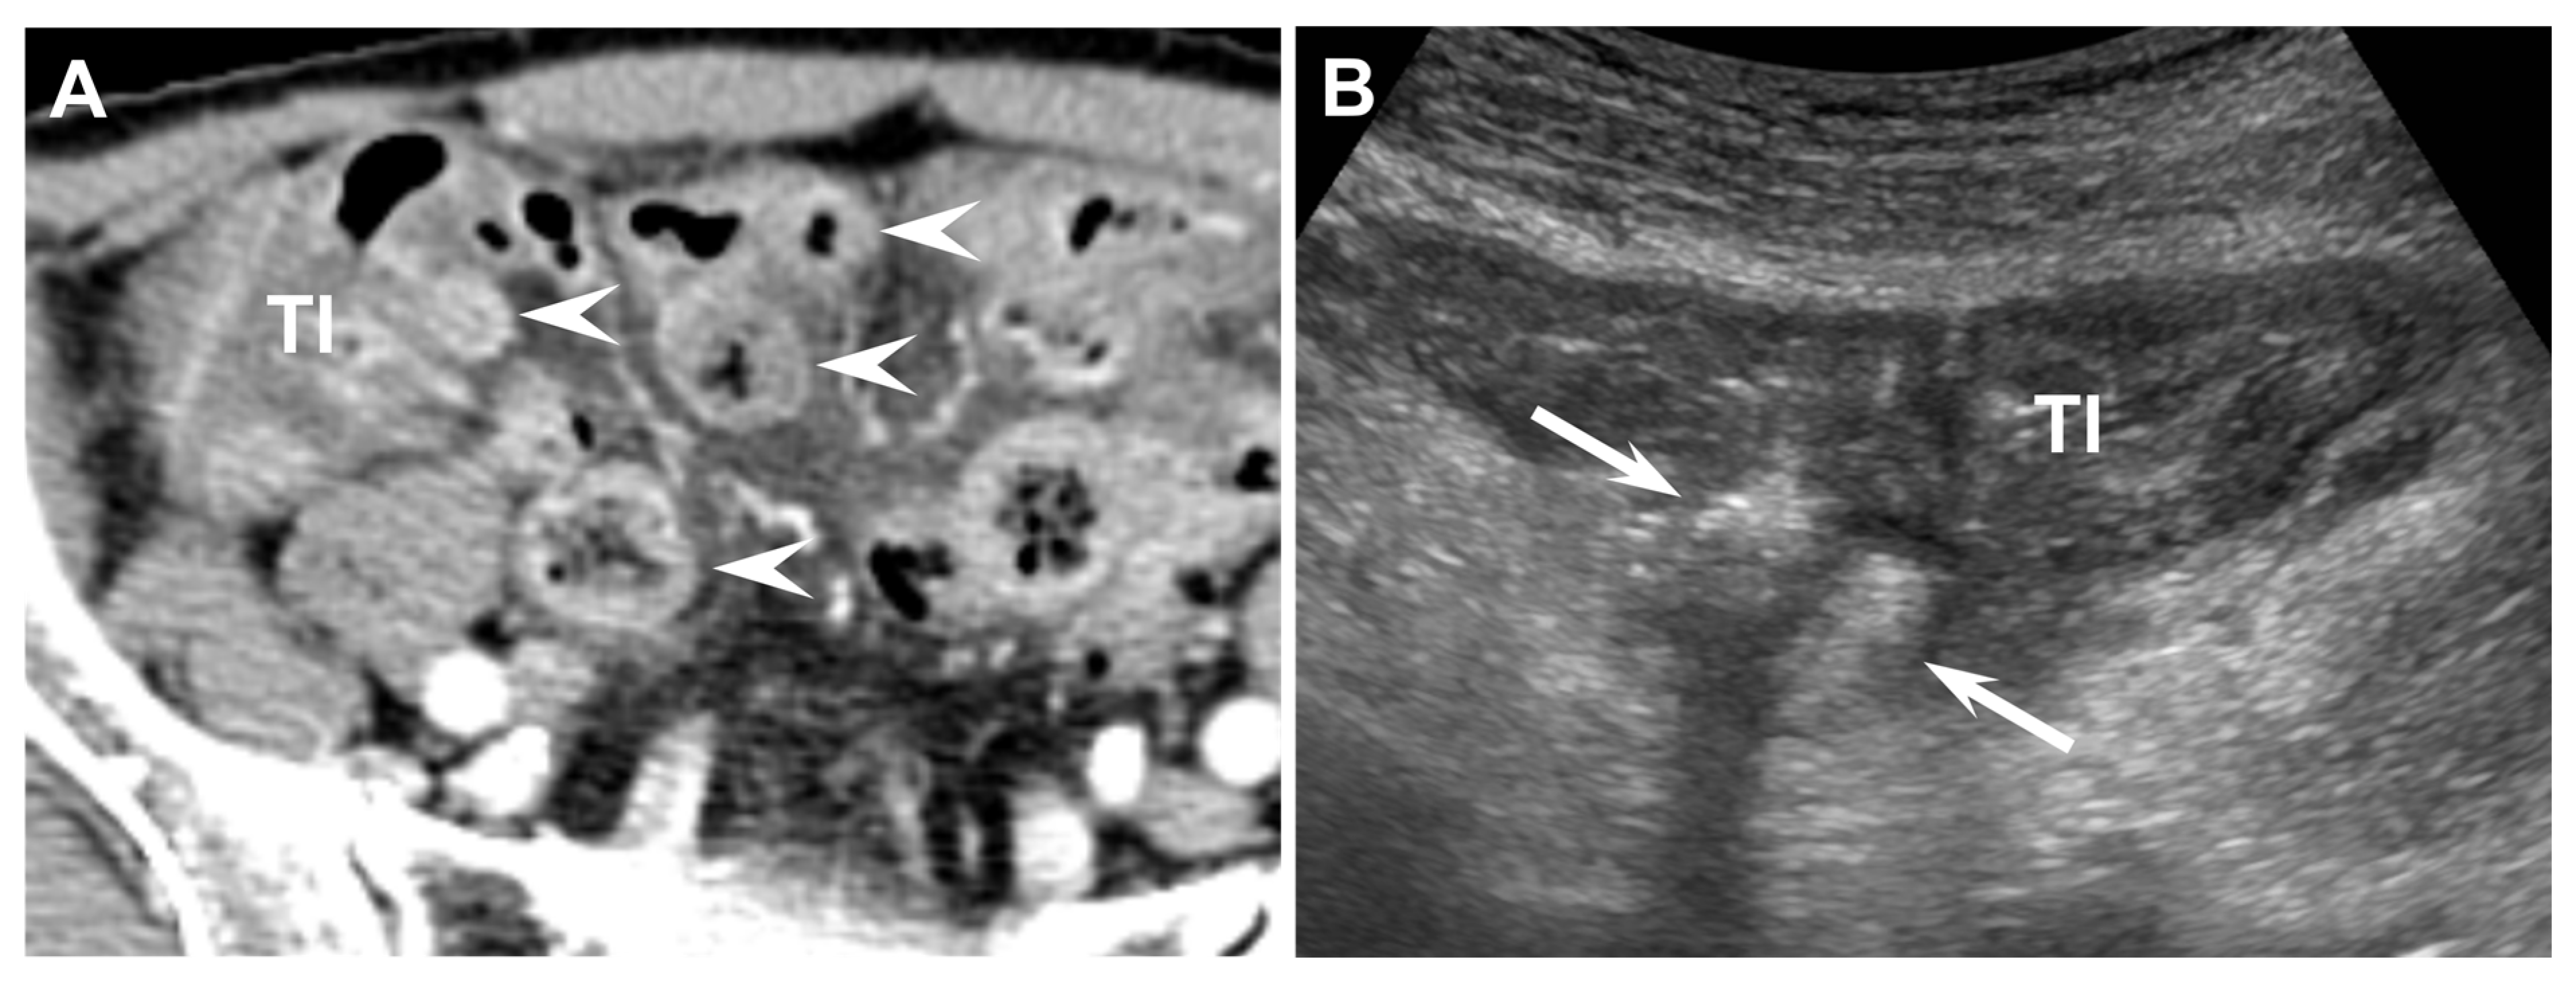

Figure 3. Seventy-eight-year-old male (patient #4) with acute ileal diverticulitis. (A) Enhanced axial CT scan shows multiple ileal diverticula (arrowheads) with or without fecalith, ileal wall thickening (TI), and mesenteric fat infiltration. (B) US scan with C5-1 convex transducer demonstrates two outpouching diverticular sacs (arrows) with central hyperechoic fecalith, ileal wall thickening (TI), and increased peridiverticular fat echogenicity.

The CT findings for acute ileal diverticulitis are summarized in Table 2. All 17 patients had ileal diverticulum along the mesenteric border. Inflamed diverticulum was seen in 16 patients (94.1%) (Figure 1). The remaining patient did not have an inflamed diverticulum at the center of ileal wall thickening with abscess; however, adjacent ileal diverticula supported the diagnosis of acute ileal diverticulitis with perforation, and barium study after 1 month demonstrated two ileal diverticula along the mesenteric border (Figure 2). Three patients had radiodense fecalith within the inflamed diverticulum (Figure 3). All 17 patients had mesenteric fat infiltration with varying degrees and ileal wall thickening. Five patients (29.4%) were diagnosed with perforated ileal diverticulitis, which had the following findings: abscess (n = 2) (Figure 2), extraluminal fluid with air (n = 3) (Figure 4), and/or focal defect in the diverticular sac (n = 2) (Figure 5). Mesenteric venous gas (Figure 4) and mesenteric venous thrombosis were seen in two patients (11.8%), respectively.

The US findings for acute ileal diverticulitis are summarized in Table 3. All patients showed outpouching inflamed diverticular sac connecting to the ileum, peridiverticular inflamed fat presenting as hyperechoic fat around the diverticulum, and increased color flow to the diverticulum and surrounding inflamed fat on CDI (Figure 1). The inflamed diverticulum exhibited variable echogenicity (Figure 2 and Figure 3). Like CT findings, eight patients had a single diverticulum and nine patients had multiple diverticula. Unlike CT, US examinations diagnosed perforated ileal diverticulitis in seven patients. The findings indicated that five patients had both abscess and extraluminal air bubble (Figure 4 and Figure 5), one patient had only extraluminal air bubble (Figure 6), and one patient had only abscess.